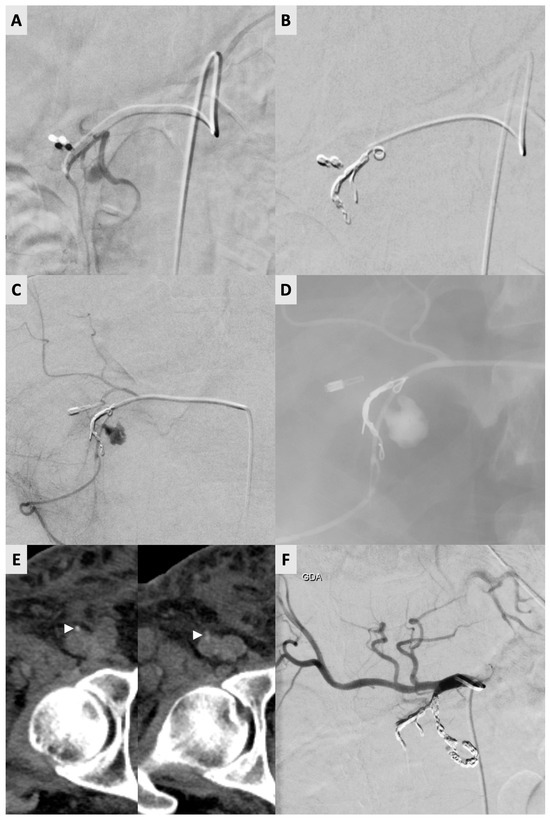

Figure 1.

A 60-year-old male undergoing endoscopic ultrasound-guided fine needle aspiration (EUS-FNA) for a pancreatic mass, complicated by duodenal hemorrhage, requiring angiographic intervention. (A) Initial angiogram revealing a pseudoaneurysm of the posterior superior pancreaticoduodenal artery (PSPDA). (B) Successful coil embolization of the gastroduodenal artery (GDA) and PSPDA was performed with favorable angiographic outcome. Hemostasis was achieved with 6F AngioSeal. (C) Recurrent symptoms 4 days after index procedure prompted a repeat angiogram confirming recanalization of the pseudoaneurysm. (D) Subsequent embolization of the pseudoaneurysm using glue was performed. Hemostasis again achieved with 6F AngioSeal. (E) Symptoms recurred 3 days later, and a follow-up CTconfirmed re-bleeding. Unenhanced CT of the right common femoral artery (CFA) showing two closely positioned AngioSeal devices (white arrowheads) seen as small high-density structures within or adjacent to the previous puncture. (F) Re-repeat definitive embolization of GDA branches with coils to address persistent bleeding was performed and patient’s bleeding symptoms resolved. Hemostasis was again achieved with 6F AngioSeal, the 3rd deployment in the same vessel in 8 days.